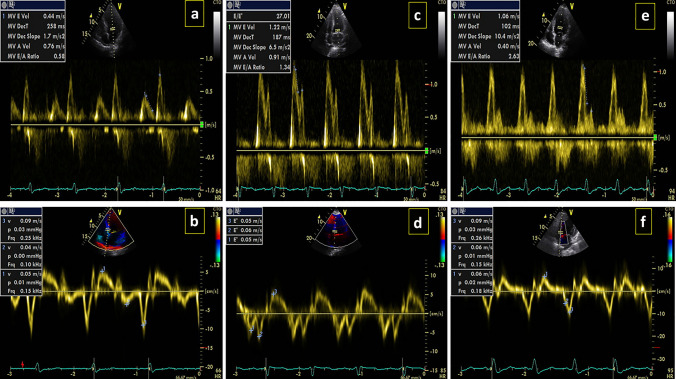

During the study period, data from 52 patients with COVID-19-confirmed infection who met the inclusion criteria were included in the present analysis. The mean age of patients was 63.4 ± 17.56 (46.2%) patients were male and 28 (53.8%) patients were female. According to echocardiographic results, 50 patients had diastolic dysfunction, of which 34 (65.4%) had grade 1 dysfunction (Fig. 1a, b), 14 (26.9%) patients had grade 2 dysfunction (Fig. 1c, d), and 2 (3.8%) patients had grade 3 dysfunction (Fig. 1e, f). The mean level of NT-proBNP in these patients was 5001.31 ± 2899.34 with the median of 1371 (24,647–473.75). The demographic and baseline characteristics of the studied patients are presented in Table 1.

Fig. 1.

Grading of diastolic dysfunction. a, b Grade 1, c, d Grade 2, e, f Grade 3